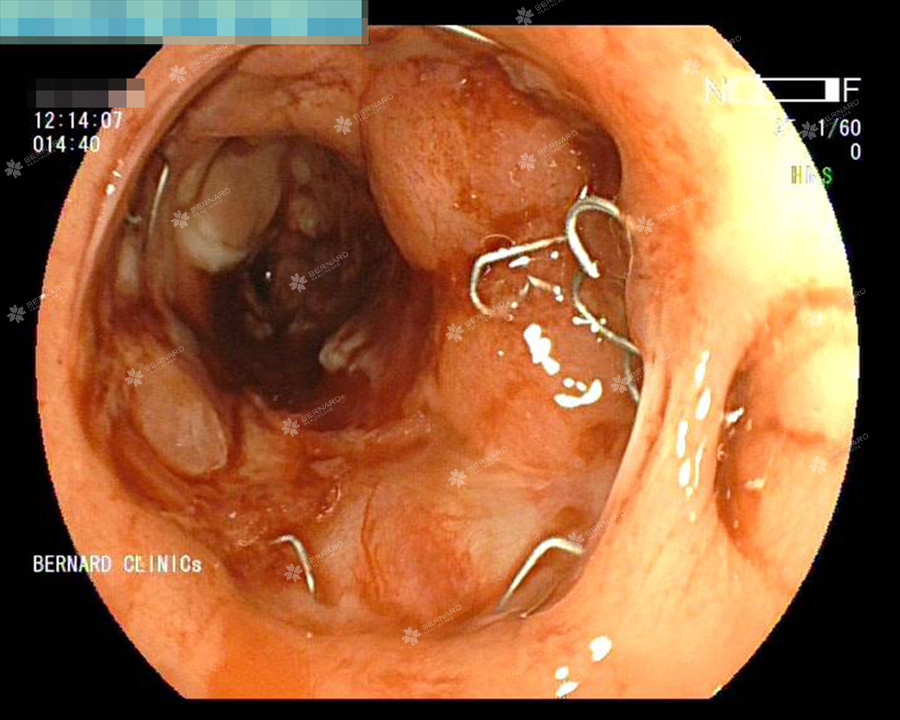

Nội soi đại trực tràng toàn bộ ghi nhận tại trực tràng cách hậu môn khoảng 10cm có khối u sùi, nhiễm cứng, hẹp lòng, phù hợp tái phát ung thư tại miệng nối.